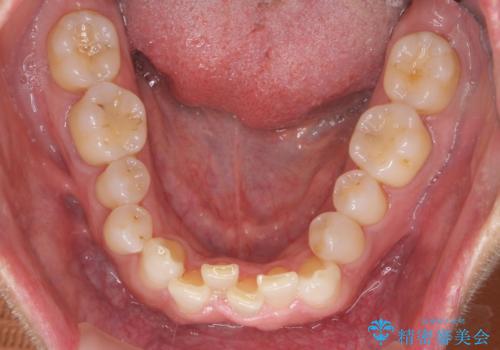

八重歯と下の歯のがたつき マウスピースで

- 右上の犬歯が目立つのが気になる、下の歯並びも治したいとのことで来院。

歯を抜かずに少し削って小さくして並べました。

並びも良くなり、患者様にも喜んでいただきました。

右上の犬歯の歯肉退縮自体は進行する可能性をお伝えしておりましたが、特に変化なく治療できました。